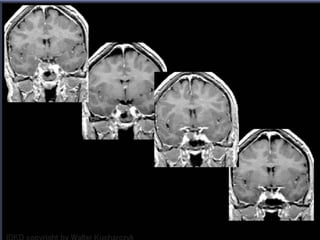

Pituitary Macroadenoma

• Usually soft

• Elevate diaphargma selle

• Often contrasted at diaphargmatic hiatus as

tumor growth into the suprasellar cistern

• Snowman shape

• *commonest large tumor of the skull base